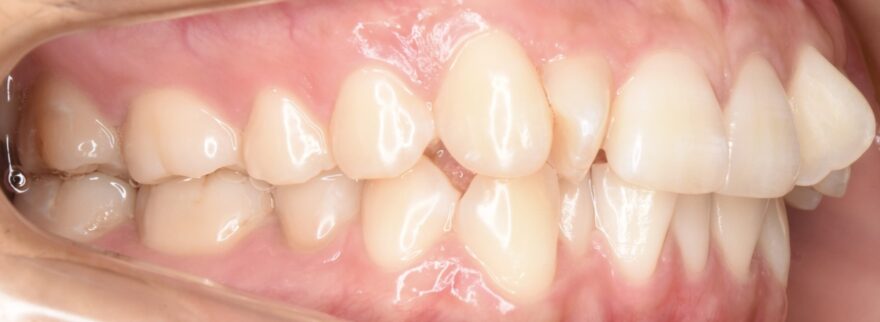

初診時の口腔内写真

前歯が捻じれてしまっています。

側方から見ると、前歯が90度以上回転していることがわかります。

最後方の奥歯が噛んでいません。